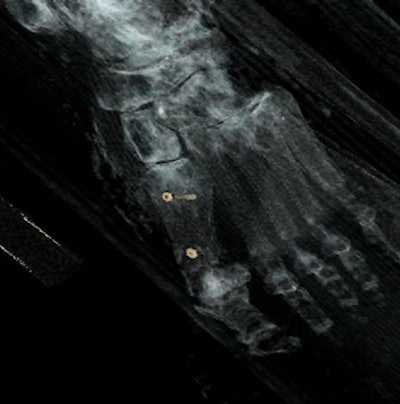

In ballistic trauma, MSCT can help to determine criteria such as location of the projectile(s) and determination of the direction of fire plus entry and exit bone wounds. Ricochets may also be detected by imaging, and the same is true of sharp trauma, with visualization of deep bone laceration or of cartilage section in some cases.

"MSCT is effective in identifying infectious lesions, and is more informative than plain x-rays. Infectious processes can affect bones, teeth, and also soft tissues, so MSCT can be very helpful in study of mummies," the researchers noted. "More rarely, bone tumors may be observed, or features secondary to metabolic changes or anemia such as cribra orbitalia, Harris lines, osteopenia, or osteoporosis. Foreign bodies may also be detected within bones."